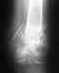

Можно и так, и так. Технически проще, наверно, hook plate. Проблема в том, что 30-50% пациентов пластина потом мешает, и приходится ее удалять.